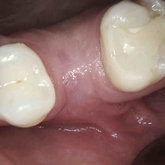

He received his Diploma in Implantology in 2016 from the University of Pretoria, which he passed with Distinction. He is also a member of the International Team for Implantology (ITI), which is based in Switzerland and offers members access to the latest research and cutting-edge techniques.

Porcelain crowns and restorations made in one appointment.

We make it a priority to incorporate the latest in dental technology in everything we do at our practice. ...